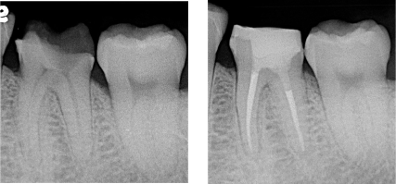

炎症を起こした神経を除去し、根管内を無菌化した上で根充およびクラウン補綴を行いました。

根管治療100,000円+ファイバーコア築造33,000円+セラミッククラウン115,500円.